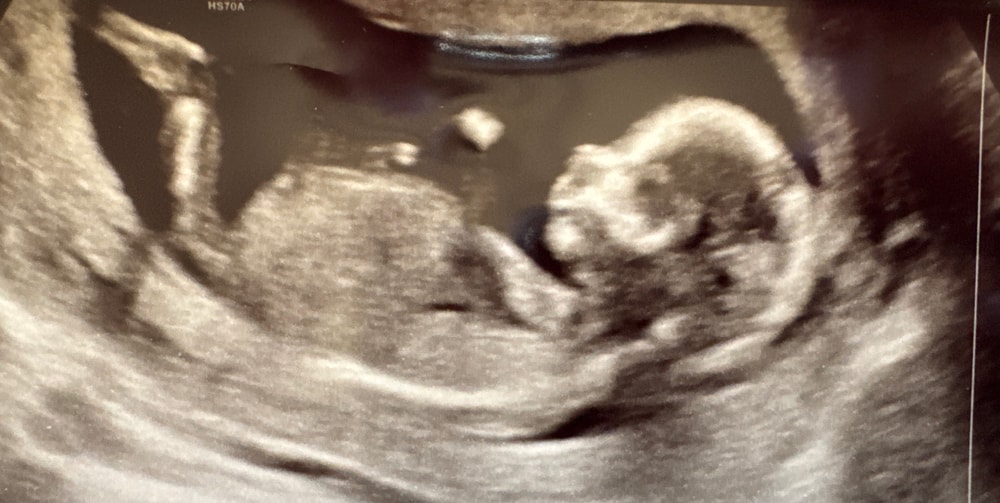

УЗИ, КТГ, доплерЗдравствуйте!У меня 14 недель и 1 день, была на узи сказали мальчик по половому бугорку, можете посмотреть пожалуйста тоже, как думаете кто у меня? Есть ощущение, что на фото часть ноги, а не половой бугорок.

По такому ракурсу даже узисты не смотрят. И тут кроме ноги ничего не видно. Когда я ходила в 15,4 она датчик поставила со стороны живота у малыша, даже спрашивать не надо было. Там висела новогодняя гирлянда с шариками. Без слов узиста было все предельно понятно.

Конечно это нога😁он не может быть таким огромным

Сдайте кровь на определение пола, я в эти гадания не верю 👌🏻